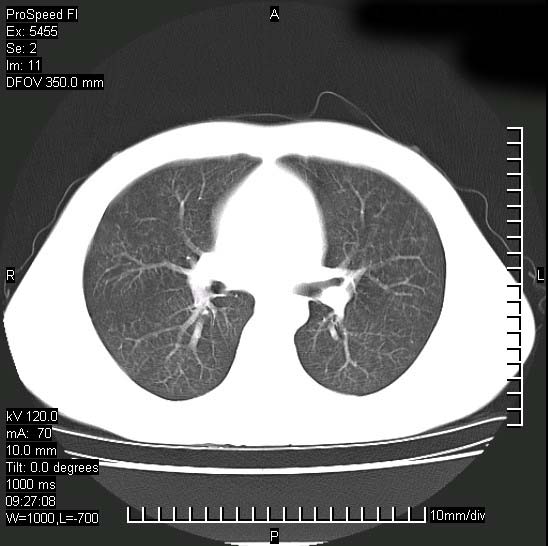

以下是引用zjzjr在2008-12-3 20:50:00的发言:[br]考虑泛细支气管肺炎,建议进一步检查除外肺出血性疾病如含铁血黄素沉着症、肺肾综合征等。

以下是引用zjzjr在2008-12-3 20:50:00的发言:[br]考虑泛细支气管肺炎,建议进一步检查除外肺出血性疾病如含铁血黄素沉着症、肺肾综合征等。

以下是引用光线在2008-12-3 20:19:00的发言:[br]双肺间质性改变。